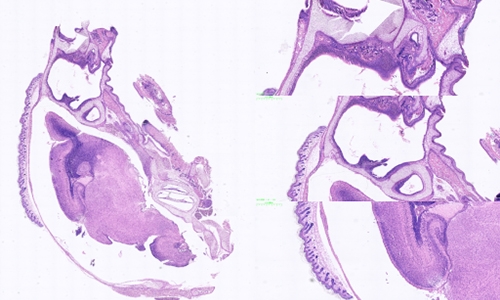

动脉粥样硬化(Atherosclerosis)是一种常见的慢性血管疾病,其病理过程涉及多种细胞和分子机制,对于人类健康造成了重大威胁。为了更好地

2023/12/12详情 >